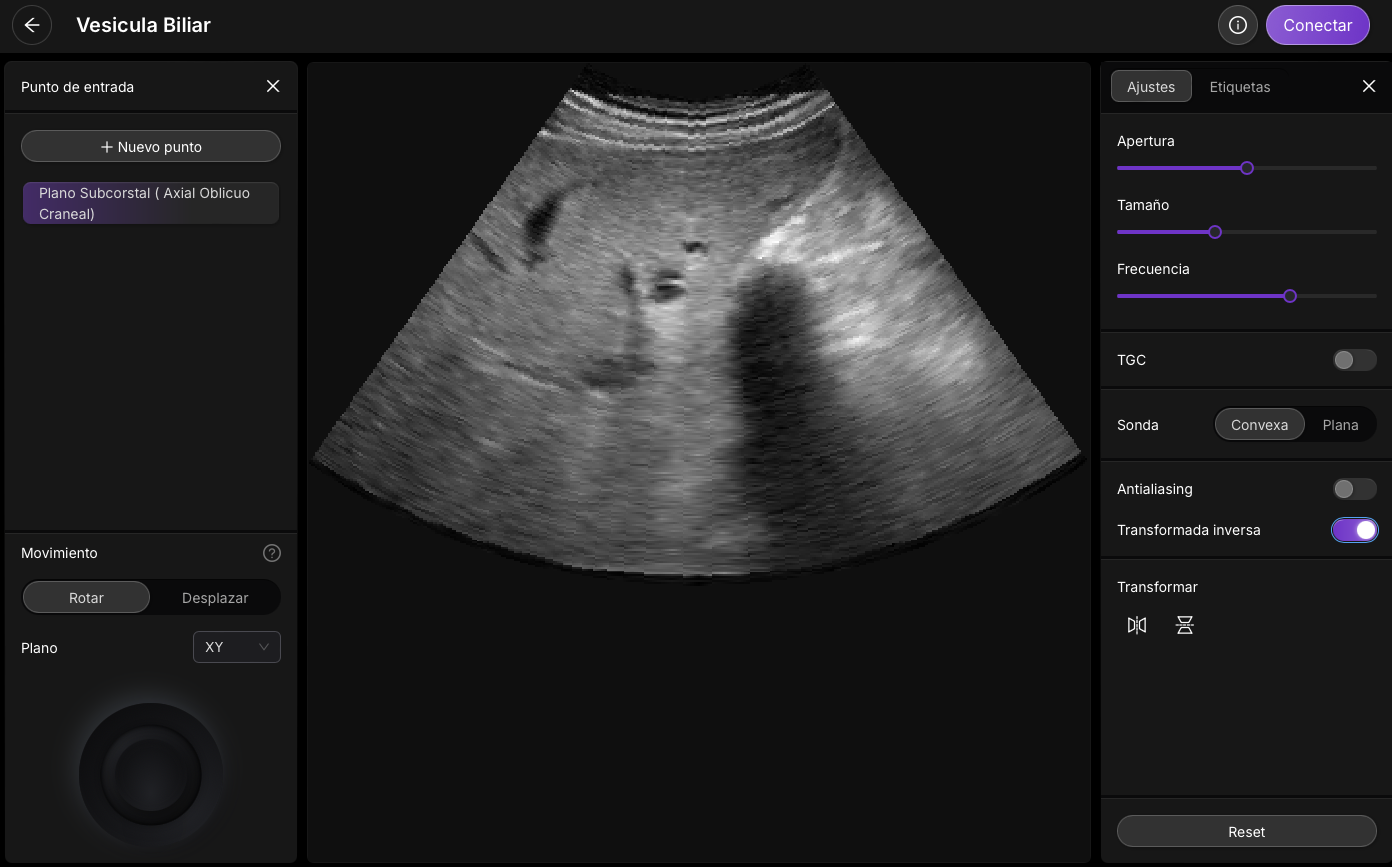

Accede al simulador interactivo docente

Simulador de Artefacto de refuerzo acústico

Simulador interactivo del artefacto de refuerzo acústico posterior

Simulación de adquisición de imágenes vesicales

Simulación de adquisición de imágenes vesicales con variaciones del refuerzo acústico según el ángulo de incidencia